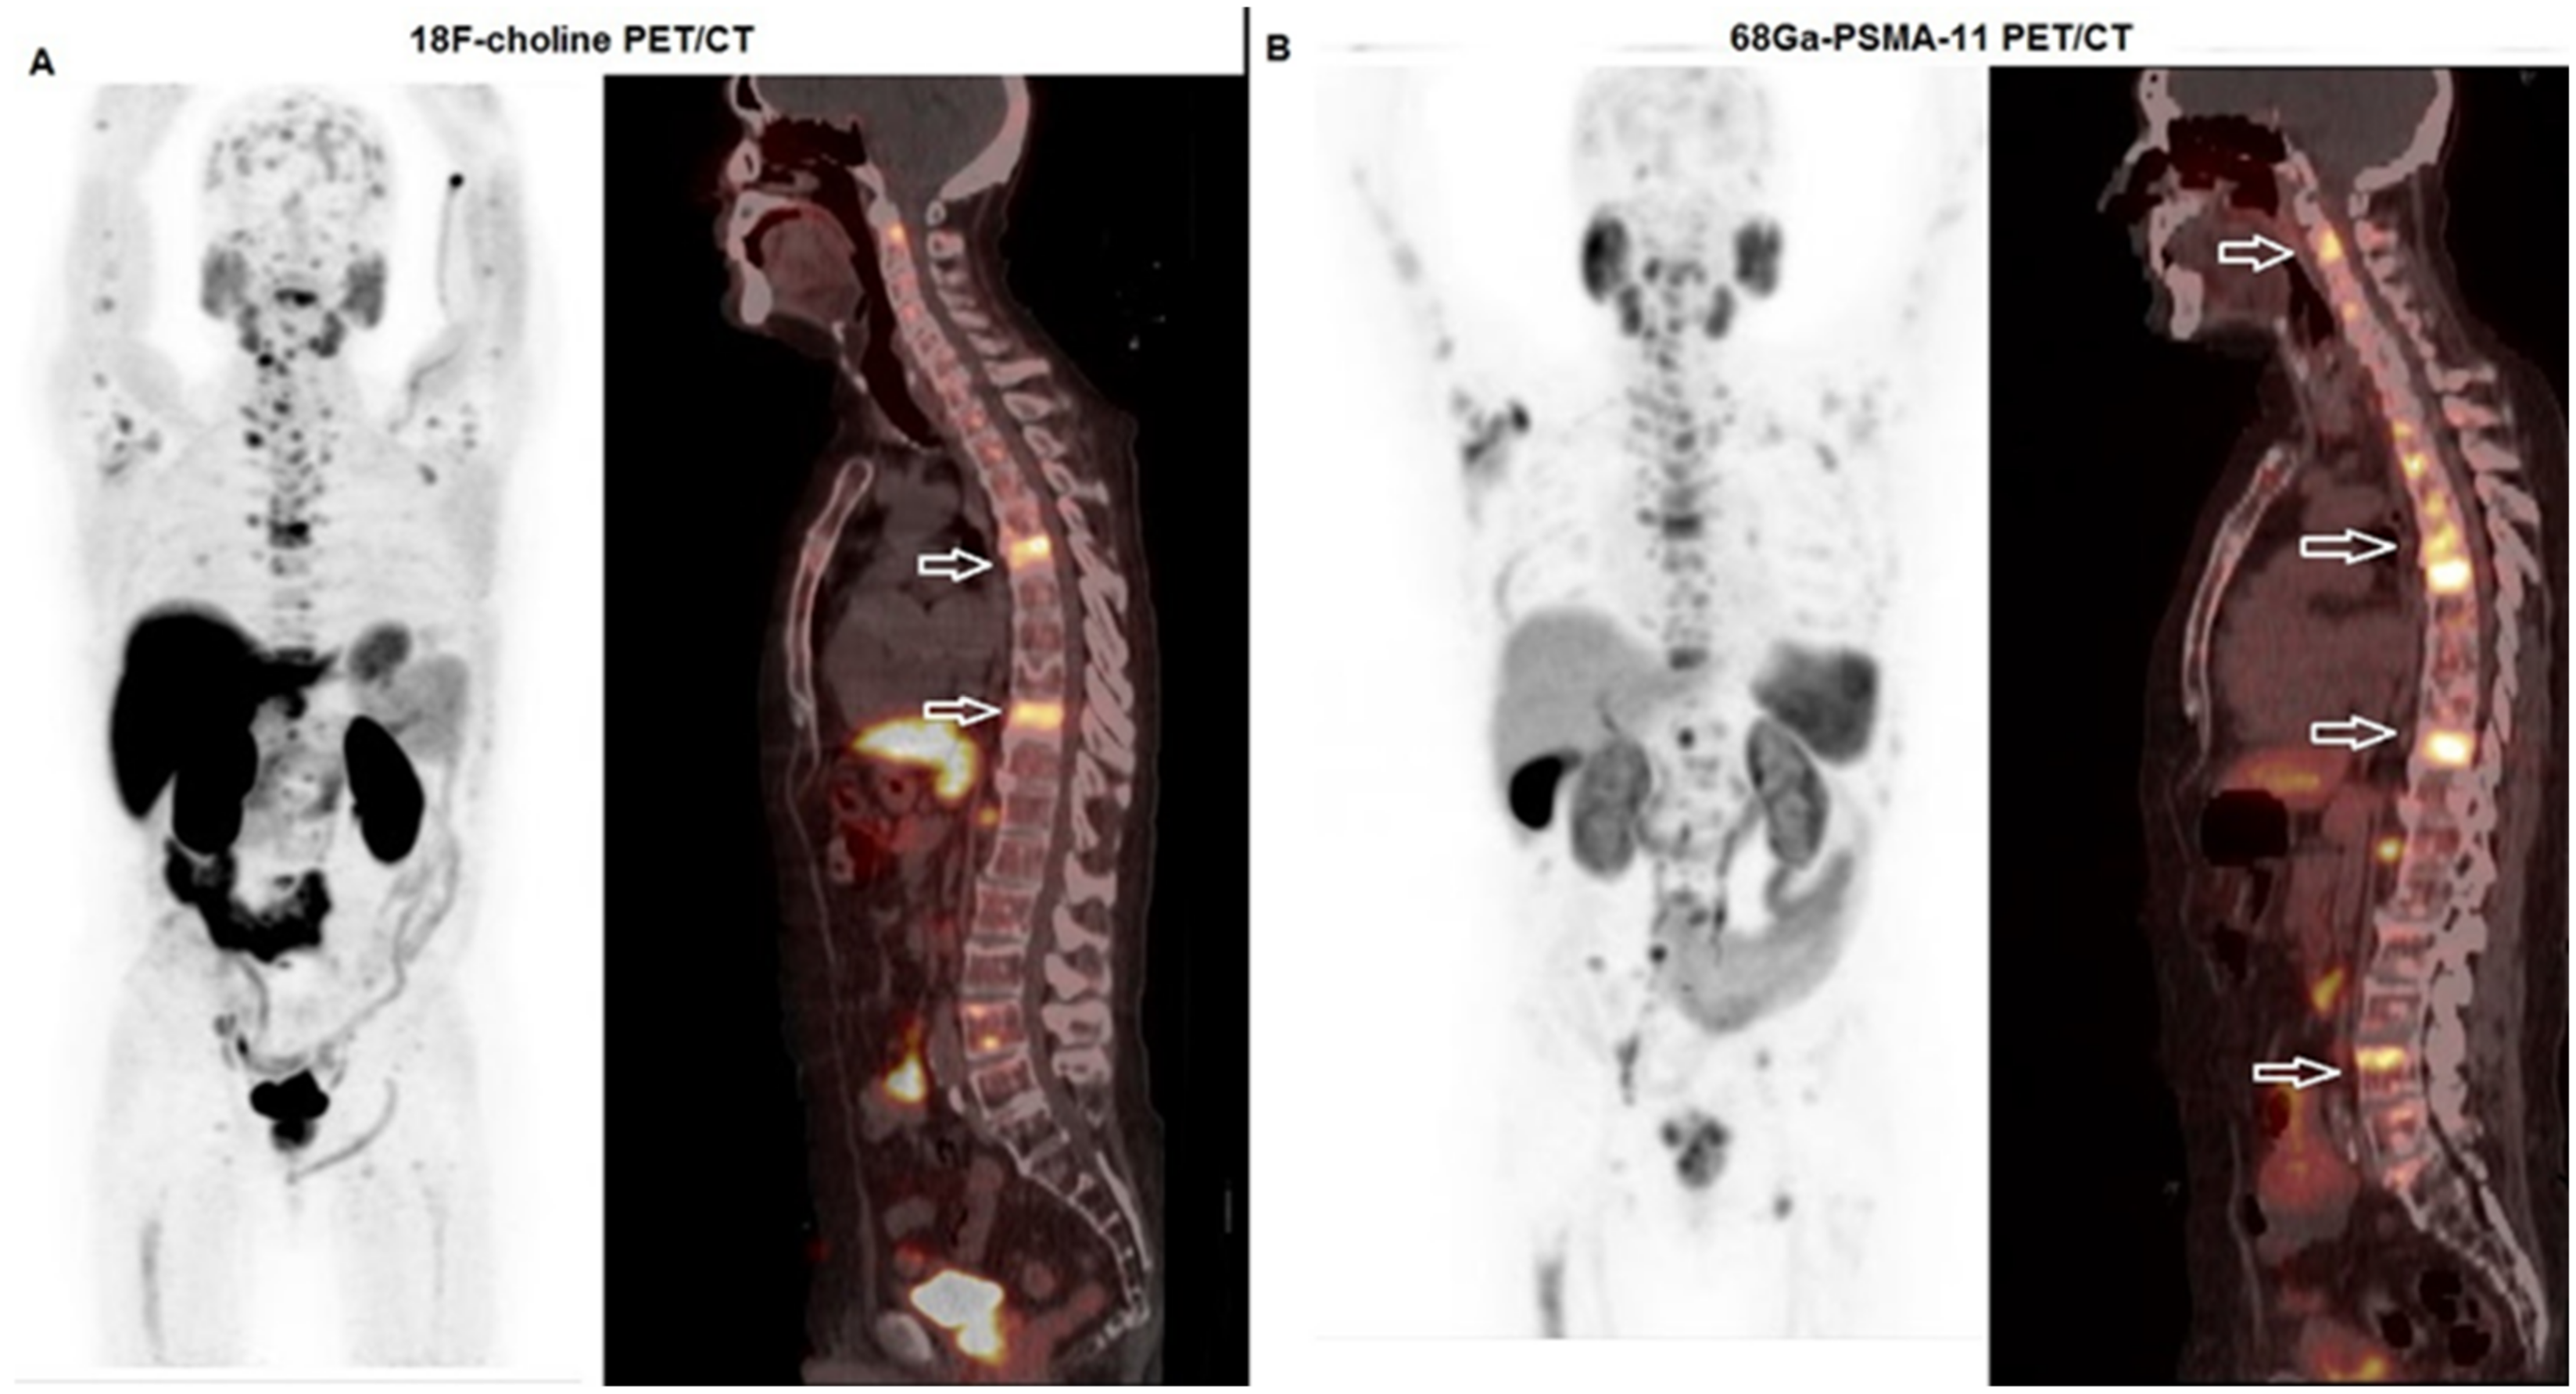

There is little evidence regarding PSMA PET and patients selection and follow-up after 223Ra-Cl2 treatment; PSMA PET may be useful in patients’ selection for 223Ra-Cl2 treatment: in fact, this imaging technique may provide additional information regarding visceral metastasis, leading to a change in the therapeutic management in some cases [59,60]. Moreover, Ahmadzadehfar et al., evaluating 63 patients who underwent 223Ra-Cl2 treatment, demonstrated a significant correlation between PSA changes and therapeutic response reported by PSMA-PET, thus highlighting the possible effectiveness of PSMA-PET in the evaluation of response to 223Ra-Cl2 treatment [61]. Figure 2 shows the case of a patient affected by mCRPC, whose overall tumor burden before 223Ra-therapy was evaluated by both 18F-choline and 68Ga-PSMA-11 PET/CT.

Figure 2.

A 71-year-old man affected by prostate cancer, diagnosed in 2009 and submitted to prostatectomy (Gleason score 4 + 3, ISUP 3, pT2 pN0). After 8 years, progressively increasing values of PSA were registered, and the patient underwent a sequence of therapeutic regimens (antiandrogen deprivation therapy, 2nd generation antiandrogen therapy with enzalutamide, chemotherapy with taxanes). In 2022, due to progressive disease at a skeletal level, he was submitted to PET/CT with 18F-choline and 68Ga-PSMA-11 before enrollment for 223Ra-therapy. (A) Whole body (left side) and fused sagittal 18F-choline PET/CT (right side) demonstrated highly increased tracer incorporation in the thoracic spine (white bordered arrows). (B) Whole body (left side) and fused sagittal 68Ga-PSMA-11-PET/CT (right side) depicted multiple PSMA-avid lesions in the cervical, thorax and lumbar spine (white arrows). Note that the extension of skeletal involvement shown by 68Ga-PSMA PET/CT is much more relevant with respect to that demonstrated by 18F-choline.